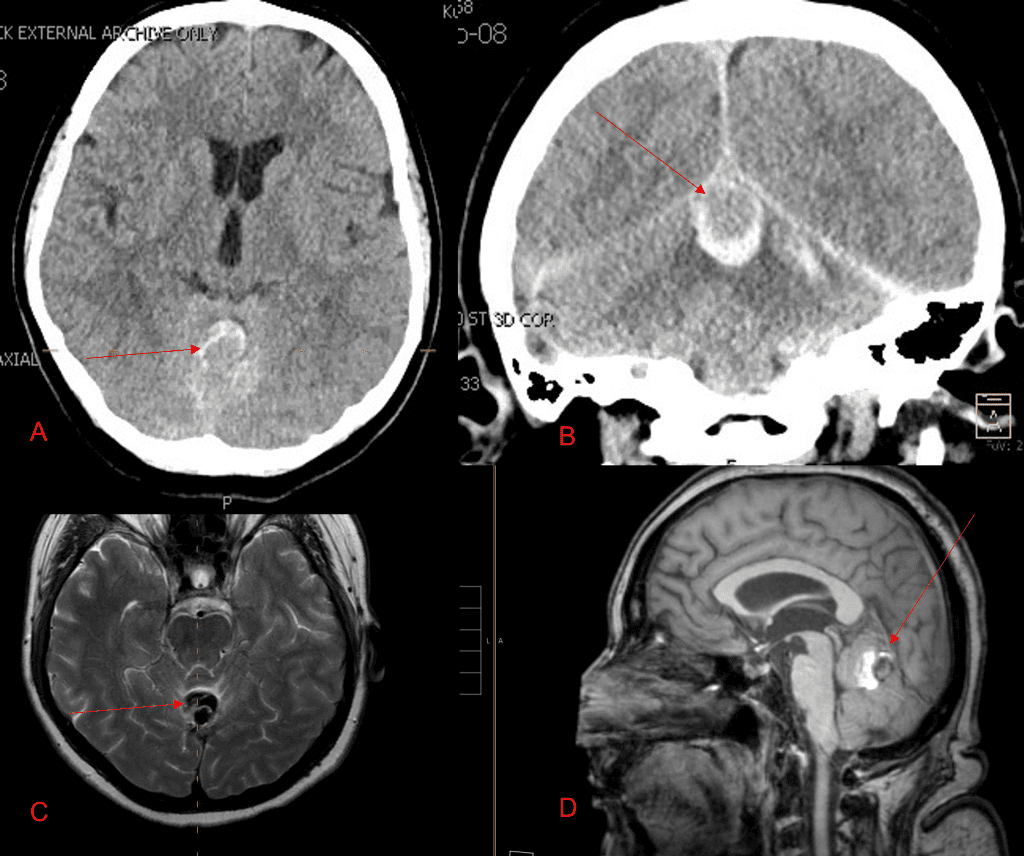

No severe neurologic deficits were observed initially. Her cerebral angiogram revealed a high flow Dural arterial venous fistulous malformation of the tentorium supplied by the bilateral external carotid and left vertebral arteries into a large venous varix within the fourth ventricle at the site of the hemorrhage. Deep venous drainage is observed into the Galenic and Straight Sinus of the posterior fossa (Figure 2).

Figure 2. [A] Ruptured Varix/Aneurysm of the Deep Venous Posterior Fossa drainage and AV shunting (arrows) [B] Posterior Meningeal Artery Fistula [C] Right Middle Meningeal Artery Fistula [D] Post embolization Left Vertebral Angiogram demonstrates resolution of the high flow and pressure A-V Shunting following successful embolization with liquid embolic (NBCA).